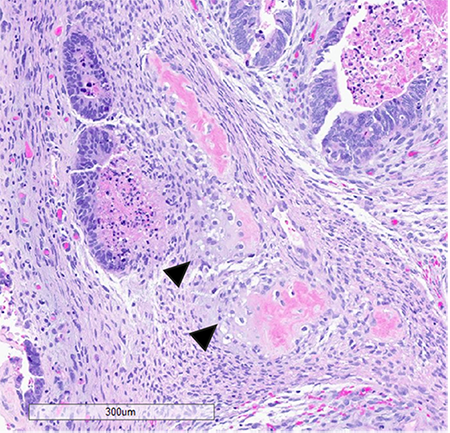

Microscopic examination confirmed carcinosarcoma [figure 3] and revealed heterologous elements, including osteosarcoma and chondrosarcoma [figure 4 and 5]. Metastatic carcinomatous component was identified in the right ovary (1.0 cm) [figure 6], left ovary (0.2 cm), as well as right para-ovarian tissue with tumor cells residing in lymphovascular spaces. The tumor was staged at pathological stage pT3a and a FIGO stage IIIA: local and/or regional spread of the tumor, invading serosa of the corpus uteri and/or adnexa. Finally, the patient was started on adjuvant chemotherapy with carboplatin and paclitaxel.

Figure 4 (left) and figure 5 (right): The sarcomatous component in this case showed heterologous elements in the form of osteosarcoma, large, atypical cells resembling osteoblasts with densely eosinophilic cytoplasm forming osteoid (fig. 3) and chondrosarcoma, atypical, neoplastic chondrocytes, and islands of mature appearing, well differentiated hyaline cartilage (fig. 4 arrow heads)